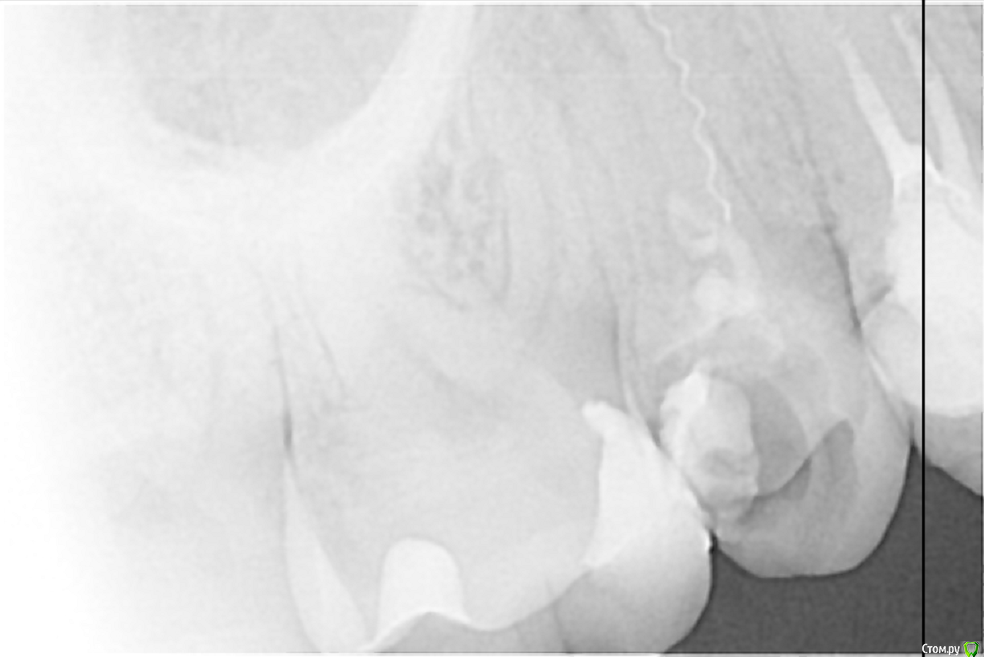

Всем доброго дня! В коем то веке появилась свободная минутка и решил поделиться с вами несколькими кейсами. Обострение хронического периодонтита 27, каналонаполнитель в нёбном канале. Коффердам, извлечение каналонаполнителя, хлорка, лимонка, УЗ, кальций. Обтурация Ah+ латеральная компакция.